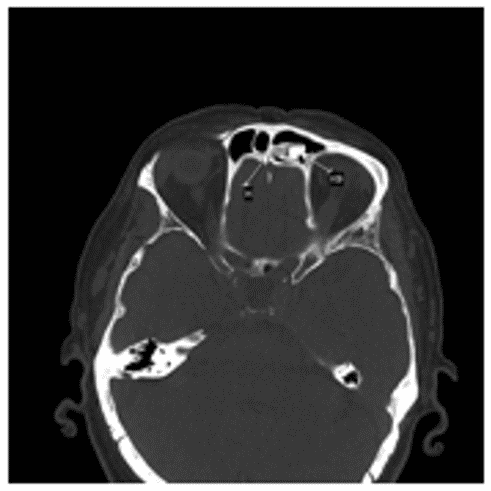

Остеобластома на КТ обычно представлена сочетанием плотной кости и участков затемнения (рисунок 4).

Рис. 4. КТ черепа, аксиальная плоскость. Гигантская остеобластома, распространяющаяся в правую орбиту, полость носа и переднюю черепную ямку

Данные КТ позволяют определить признаки локально агрессивного роста остебластомы, место ее исходного роста, наличие/отсутствие распространения опухоли за пределы околоносовых пазух.